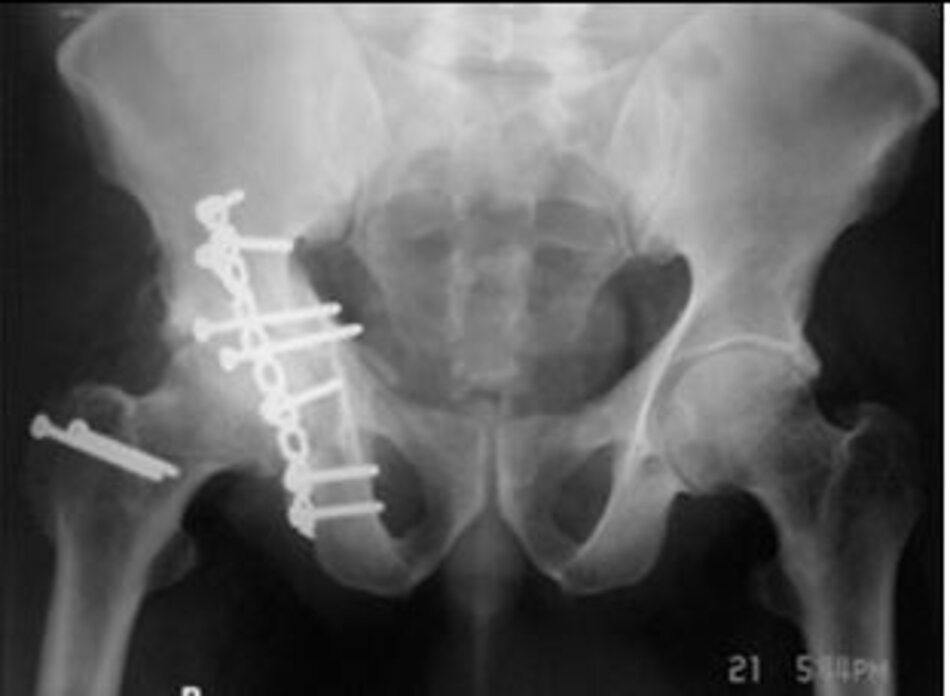

Phẫu thuật Vỡ xương chậu phức tạp

Phẫu thuật đường trước:

Hình ảnh vỡ xương chậu phức tạp

Hình ảnh đường mổ và phim chụp sau mổ đạt kết quả đúng giải phẫu